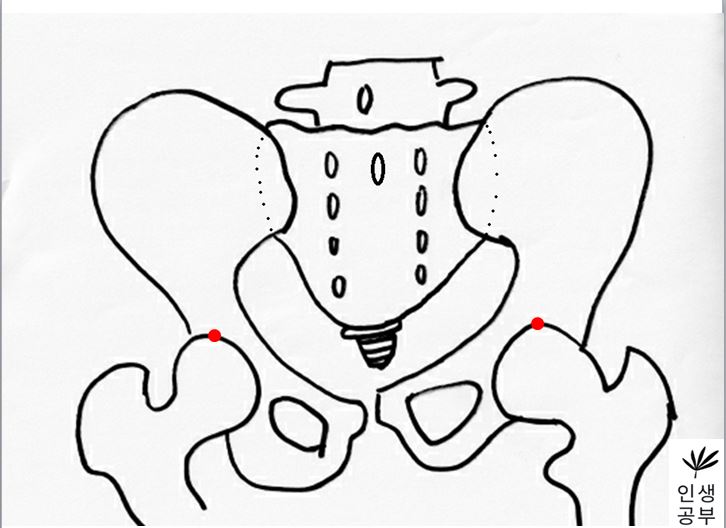

2) 대퇴골두(Femoral head) 최상단에 양쪽에 각각 한개씩 점을 찍어줍니다.

3) 두 점을 연결하는 선을 긋습니다. 이 선의 이름은 대퇴골두선(FHL : Femur Head Line)이라고 합니다.

6) 1번째나 2번째 엉치뼈 결절(sacral tubercle) 정가운데 찍은 점에서 대퇴골두선(FHL : Femur Head Line)을 기준으로 수직인 선을 긋습니다.

선을 그었을 때 점이 있는 쪽 골반이 IN이 됐다는 뜻이고, 없는 쪽은 EX 되었다는 뜻입니다.